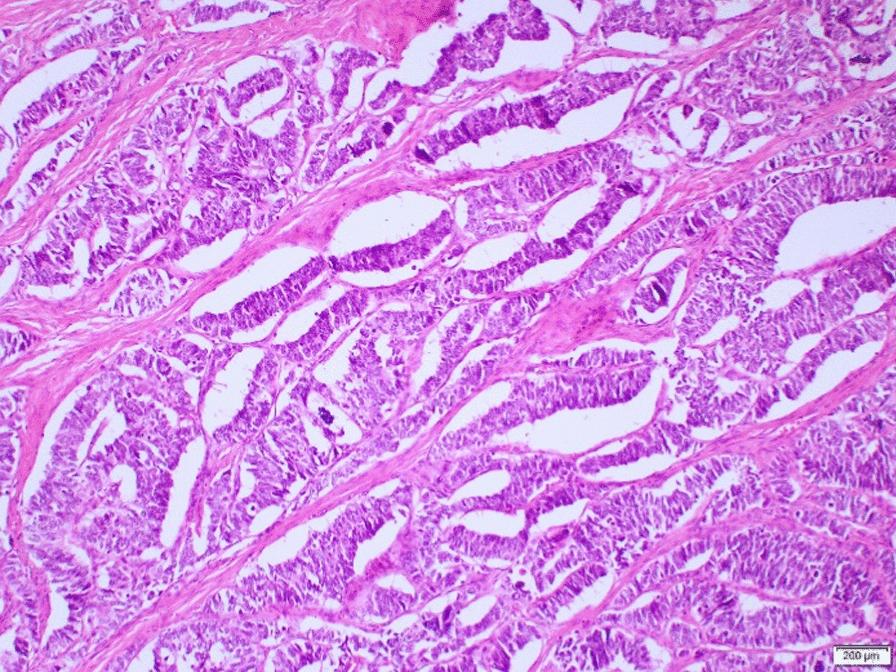

We are reporting a case of primary ovarian neuroendocrine neoplasm in association with an epithelial borderline tumor. She is a 50-year-old Filipino woman who presented with nonspecific symptoms. Initial imaging revealed a large mass with suspicion of widespread metastasis. However, further imaging and laparotomy revealed early-stage neuroendocrine neoplasm, a large borderline epithelial tumor, with no evidence of pulmonary metastasis, despite having pleural effusion. She was lost to follow-up, presented again after a year with evidence of residual disease/metastasis, and was treated with chemotherapy.

我们报告一例原发性卵巢神经内分泌肿瘤合并上皮性交界性肿瘤的病例。患者为一名50岁的菲律宾女性,出现非特异性症状。初始影像学检查发现一个大肿块,怀疑有广泛转移。然而,进一步的影像学检查和剖腹手术显示为早期神经内分泌肿瘤,一个大的交界性上皮性肿瘤,尽管有胸腔积液,但无肺转移证据。她失访了,一年后再次就诊,有残留疾病/转移的证据,并接受了化疗。